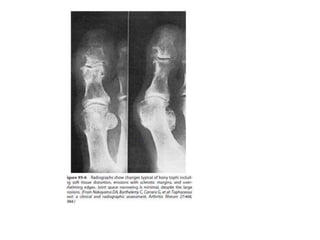

GOUT

• The three stages of gout are asymptomatic hyperuricemia, acute and

intercritical gout, and chronic gouty arthritis.

• Podagra is the classic monoarthritis of the first metatarsophalangeal joint, but

other lower limb joints can be affected.

• Tophi are indicative of the diagnosis.

• Routine radiographs frequently show no bony abnormalities

but may identify erosions after repeated or prolonged attacks.

• Diagnostic ultrasound and MRI can identify synovial fluid for

aspiration, tophi, and erosive disease

GOUT • The threestages of gout are asymptomatic hyperuricemia, acute and intercritical gout, and chronic gouty arthritis. • Podagra is the classic monoarthritis of the first metatarsophalangeal joint, but other lower limb joints can be affected. • Patients tend to be obese males, aged 40 to 50 with hypertension, and consumers of excess alcohol. • Increasingly, postmenopausal females with low estrogens . Many drugs raise serum urate levels and predispose to gout attacks, especially diuretics ,ethambutol ,pyrizinamide • Tophi are indicative of the diagnosis. • Blood Investigations reveal increase in White cell count, ESR,and CRP are raised • Serum uric acid may be raised, but levels are low in 33% during acute attacks. • Renal and liver function should be assessed.

• Needle-shaped uricacid crystals (that are negatively birefringent under polarized light) are present in synovial fluid or tophi aspirate and confirm the diagnosis. • Routine radiographs frequently show no bony abnormalities but may identify erosions after repeated or prolonged attacks. • Diagnostic ultrasound and MRI can identify synovial fluid for aspiration, tophi, and erosive disease